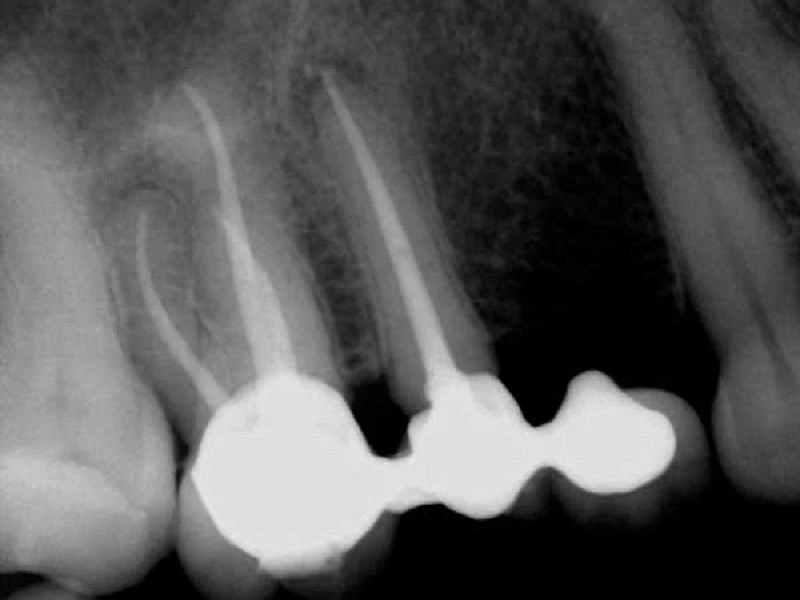

- Lựa chọn, sử dụng vật liệu và kỹ thuật bịt kín không đúng cách. Một vật liệu như Thermafil rất nhạy cảm với kỹ thuật và nếu không được sử dụng đúng cách chắc chắn sẽ dẫn đến suy tủy răng. Sau khi bị che khuất, nó có thể xuất hiện một cách hoàn hảo trên phim chụp X quang với vật liệu dường như được lấp đầy đến đỉnh. Trong trường hợp không thành công, bạn có thể thấy một vết phóng xạ lớn quanh chóp và điều này có thể cho thấy khả năng bị thủng chóp.

Một số u phóng xạ quanh miệng (PARLs) có thể tồn tại đến 5 năm sau khi điều trị tủy răng. Một yếu tố góp phần vào sự hiện diện kéo dài của PARL là kích thước của tổn thương ban đầu, do đó các tổn thương lớn hơn sẽ có xu hướng tồn tại lâu hơn và chữa lành với tốc độ chậm hơn.

Vị trí của tổn thương là một yếu tố khác có thể góp phần làm cho quá trình lành thương kéo dài. Các tổn thương ở xương dày đặc hơn, chẳng hạn như xương hàm trước, có xu hướng chữa lành chậm hơn các tổn thương ở xương hàm mỏng, ví như răng hàm trên sau.